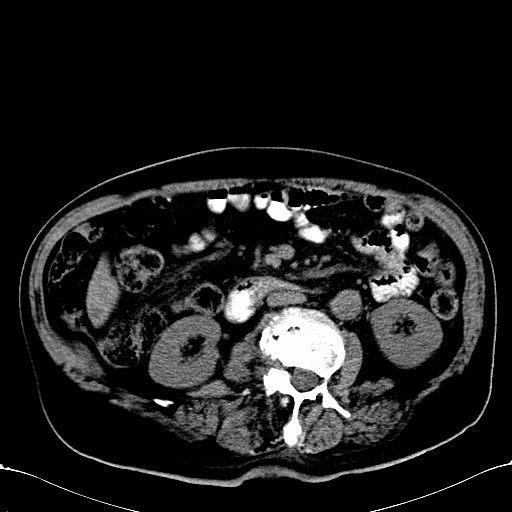

标题: CT28270:胰管扩张,肝多发占位 [打印本页]

标题: CT28270:胰管扩张,肝多发占位

患者,男,75岁。

考虑胰腺钩突癌并肝内转移,建议强化明确。

1)考虑胰头癌并肝脏多发性转移;建议行ct增强扫描检查。2)胃窦癌?建议行胃镜检查。

胰管有扩张,位置比较低,同意楼上几位高手意见。肝内转移可能大,建议增强。

肝脏多方低密度结节,边缘模糊,考虑多发转移,胰管明显扩张,建议增强扫描钩突情况

肝脏多发低密度灶,胰头似呈低密度,胰管扩张,建议增强,

胰管显著扩张,但胆总管未见扩张征象,不太符合胰头占位!考虑慢性胰腺炎.胃窦占位并肝内转移可能!mrcp胃镜增强一起上!